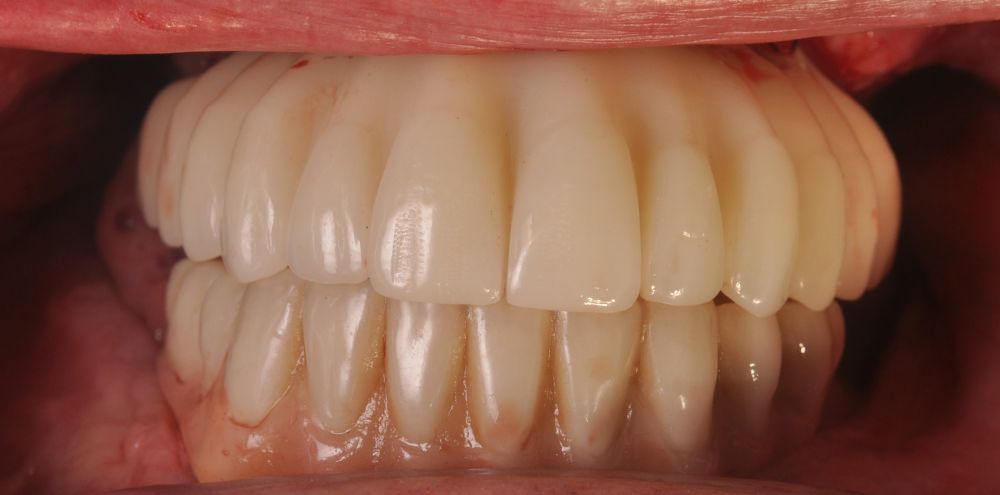

Clinical Case: A subperiosteal sintered titanium structure was fabricated with six transepithelial connections that were rehabilitated with an immediate implant supported fixed prosthesis made of PMMA. Two months later, a sintered chromium-cobalt framework with machined bases covered with acrylic resin teeth was fabricated as the final restoration. At one year follow-up, the case remains stable.